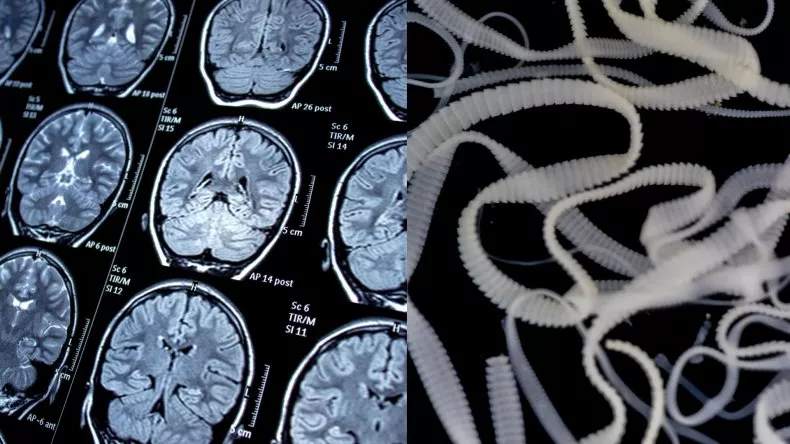

Thái Nguyên: Người đàn ông lên cơn co giật, tưởng đột quỵ, ngỡ ngàng là sán lợn làm tổ trong não

Người đàn ông 58 tuổi ở Thái Nguyên bất ngờ bị co giật, méo miệng, rụt lưỡi không nói được. Gia đình lo đột quỵ nên đã nhanh chóng đưa đi cấp cứu thì ngỡ ngàng khi phát hiện sán lợn làm tổ trong não.